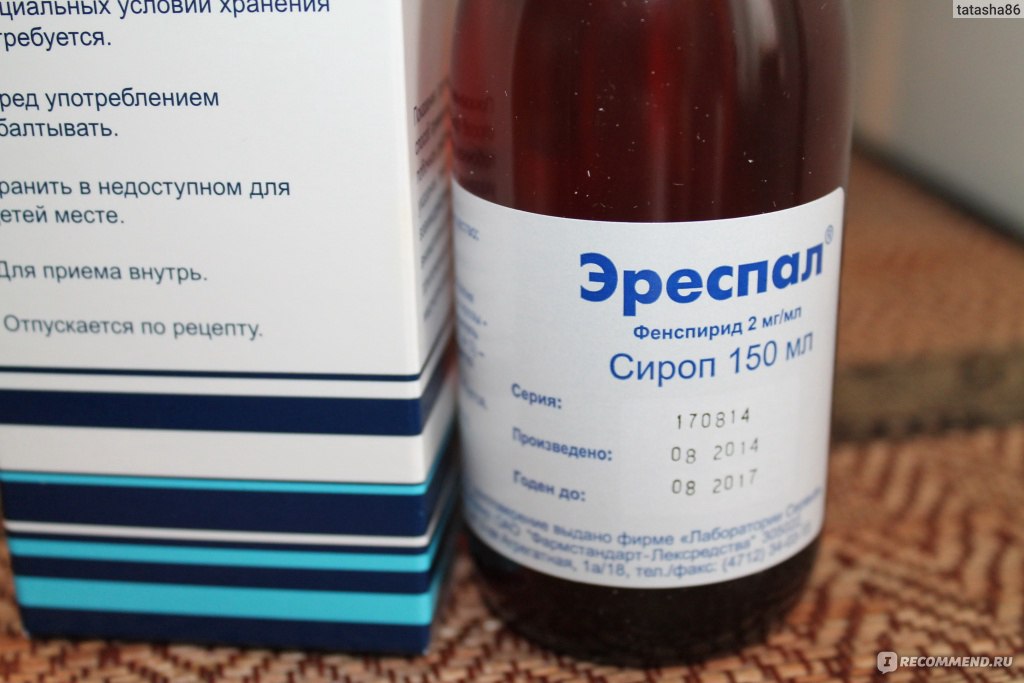

Эреспал детям